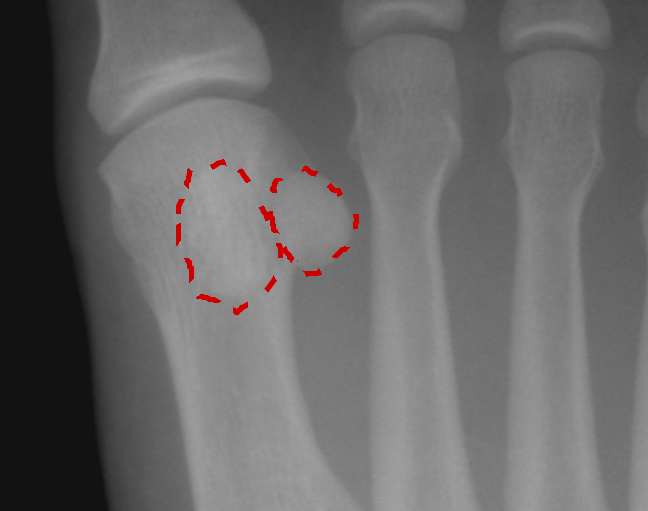

Ossa sesamoidi

- Descrizione: Ossa piccole e rotonde che sono incluse in un Tendine e che aiutano nella funzione della Articolazione. Le più conosciute sono quelle dell'alluce.

- Senso biologico [!]: Ossa la cui funzione è agire come perno per potenziare la forza che realizza l'articolazione alla quale appartengono. Nell'alluce aiutano a mantenere l'equilibrio del corpo.